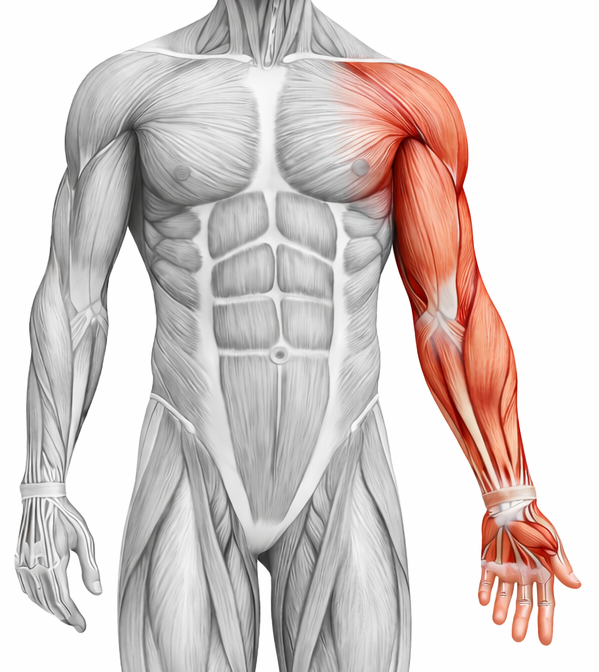

Upper Limb

Learn Gross Anatomy of the Upper limb, including functional aspects, joints, nerves, vessels, and its clinical aspects.